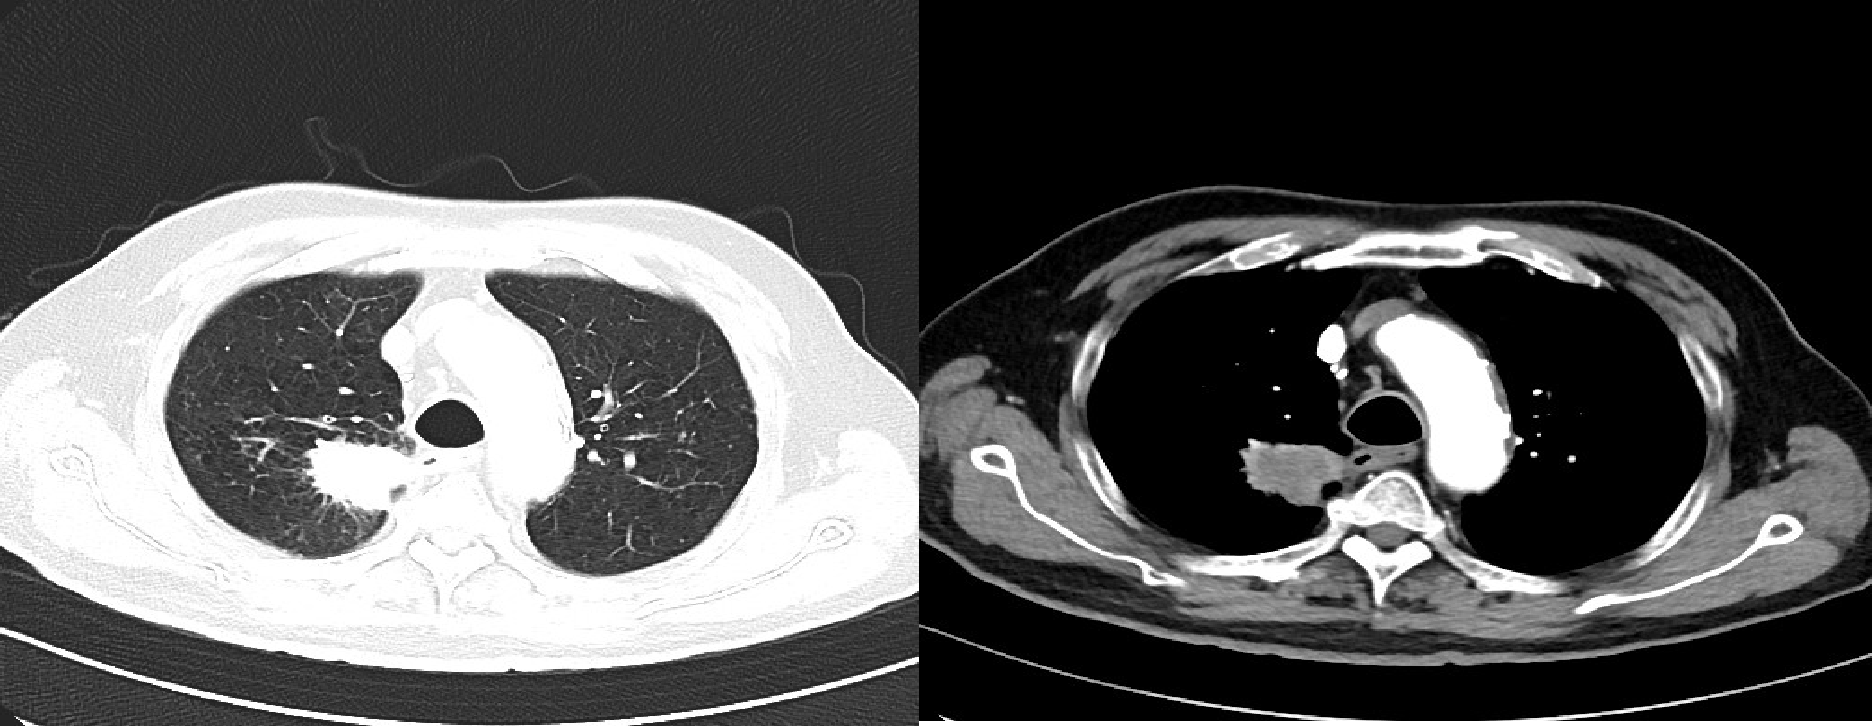

2022-02 胸腹部增强CT(图1):右肺上叶周围型肺癌影像表现,COPD、右肺下叶及左肺上叶纤维灶、结节灶,邻近支气管扩张影像学表现;双侧肾上腺增粗,左侧肾上腺结节灶,符合双侧肾上腺转移瘤影像表现,左肾囊肿。

2022年3月,患者至外院住院,拒绝手术,常规口服卡培他滨化疗+右肺病灶放疗(DT 5Gy×11f)。2022-3-30来院复查胸部CT(图2)提示稳定。

2023年4月,复查胸部CT(图4):符合右肺上叶病变治疗后复查表现,右肺下叶及左肺上叶纤维灶、结节灶,邻近支气管扩张;COPD影像表现,左侧肾上腺结节;右肺上叶肿瘤局部进展。

2023年9月16日,患者因气喘,复查胸腹部增强CT(图5):符合右肺上叶病变粒子植入表现、符合右肺下叶及左肺上叶纤维灶、结节灶,邻近支气管扩张、COPD,左侧肾上腺结节。痰培养:铜绿假单胞菌。后多次因肺炎给予抗炎治疗。

2024年4月,查胸部强化CT(图7):符合右肺上叶病变粒子植入表现,较前略增大;符合右肺下叶及左肺上叶纤维灶、结节灶,邻近支气管扩张;COPD、右侧胸腔积液、左侧肾上腺结节较前大致相仿。患者家属拒绝再次活检及静脉化疗。